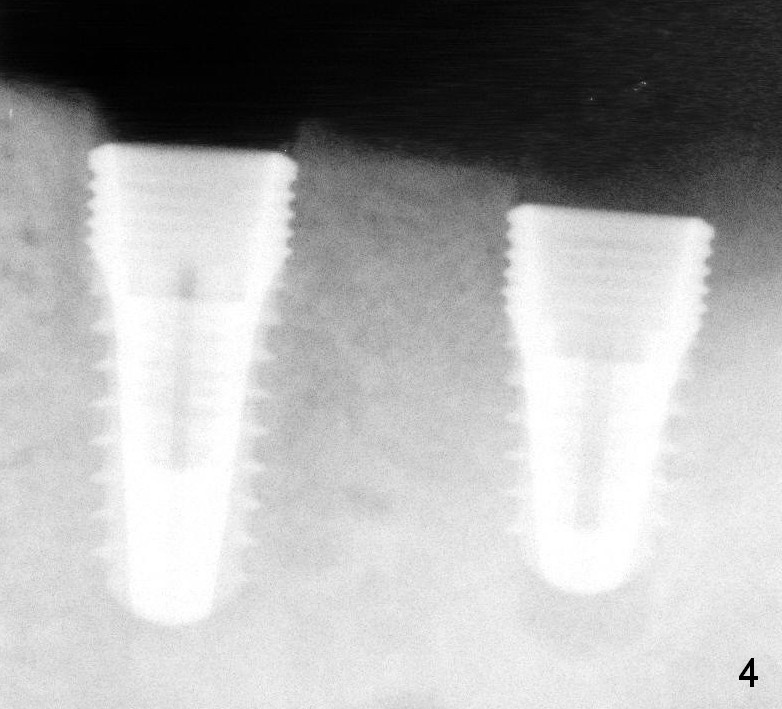

Immediately (Fig.3,4) and 3 months (Fig.8) post placement of 3x11 mm 1-piece implant at #20 (Fig.3) and 4.5x10 and 4.5x8 mm implants at #19 and 18, respectively.